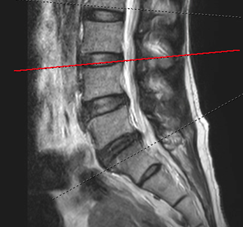

病患A右圖脊椎MRI橫切面腰椎3-4節顯示椎管內明顯狹窄。

診斷以病史與神經學檢查 為主。當臨床懷疑神經受壓、症狀持續或需規劃介入/手術治療時,醫師常會安排 MRI(磁振造影) 或必要時的 CT,以確定壓迫的節段、程度與合併病變(例如椎間盤突出或滑脫)。